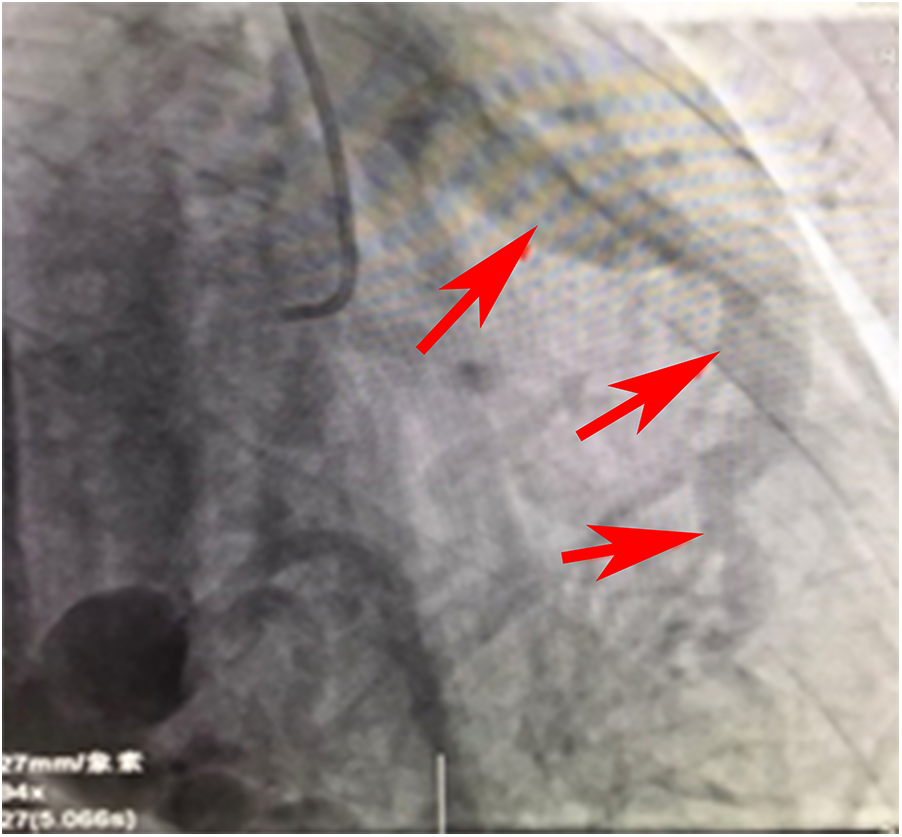

Figure 2

Angiographic image of the RCA draining into the pulmonary artery.

Figure 2 is a continuous animation of the angiography in Figure 1. The angiography shows that the right coronary artery communicates with the pulmonary artery and flows into it. The red arrow indicates that the blood flows into the pulmonary artery.